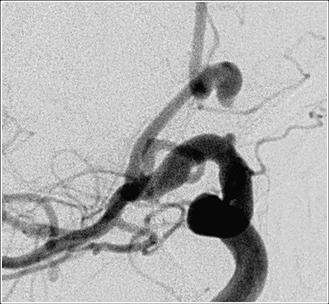

If an aneurysm bleeds, then CT scan is typically done to confirm the bleed and for evaluation of the aneurysm the best diagnostic tool available currently is a catheter angiogram.

The modern treatment of aneurysms include surgical clipping, endovascular coiling, floater diversion, vessel sacrifice and observation of the aneurysm. (Figures 3, 4, and 5). The selection of therapy depends upon multiple factors including patient's age, disease state, medical conditions, aneurysm size and location.

ruptured before 2a

ruptured after 2a

Figure 3. Before Treatment: Hemorrhagic stroke from ruptured intracranial aneurysm.

Figure 4. After Treatment: Bleeding is arrested using detachable coil.

ruptured after

Endovascular occlusion of aneurysms includes the use of detachable coils. This is a angiographic procedure where a small soft catheter is introduced into the blood vessel from the leg artery. From there the catheter is carefully threaded up into the brain and the tip of the catheter is placed in the aneurysm (figure 6). Then through the catheter small soft coils are introduced into the aneurysm to block it completely (figure 7).